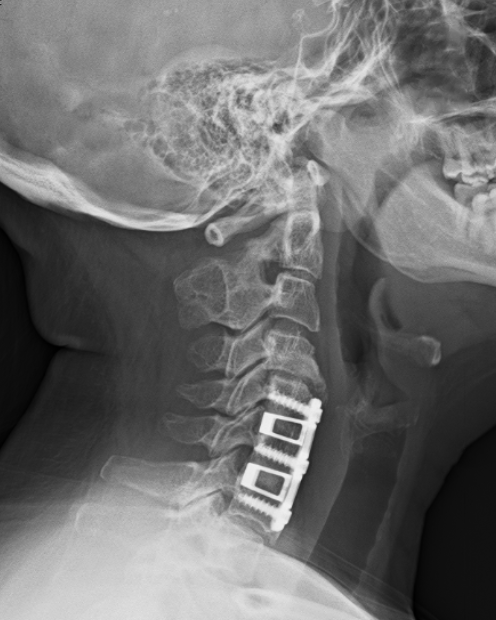

10 years ago today I had my first spinal surgery (yes, first…more on that in a minute…) To say it changed my life would be the understatement of the decade. I went from a daily headstand practice to barely being able to lift a glass of water practically overnight. The kicker is that I was “really healthy” (thin, vegetarian, and TEACHING yoga) and “nothing happened” to me. There was no accident or injury; just a lot of stress and crappy discs. Before I knew it, I was waking up from surgery with 2 replacement cages & a plate fusing 3 vertebrae.

- I think my x-rays are really cool and wanted to share them!

I hope you’ve enjoyed this little tour of my spine (cross your fingers this is the last intervention!) and as always, if I can be of service to you, please do not hesitate to reach out to schedule a Complimentary Design Discovery Consultation.